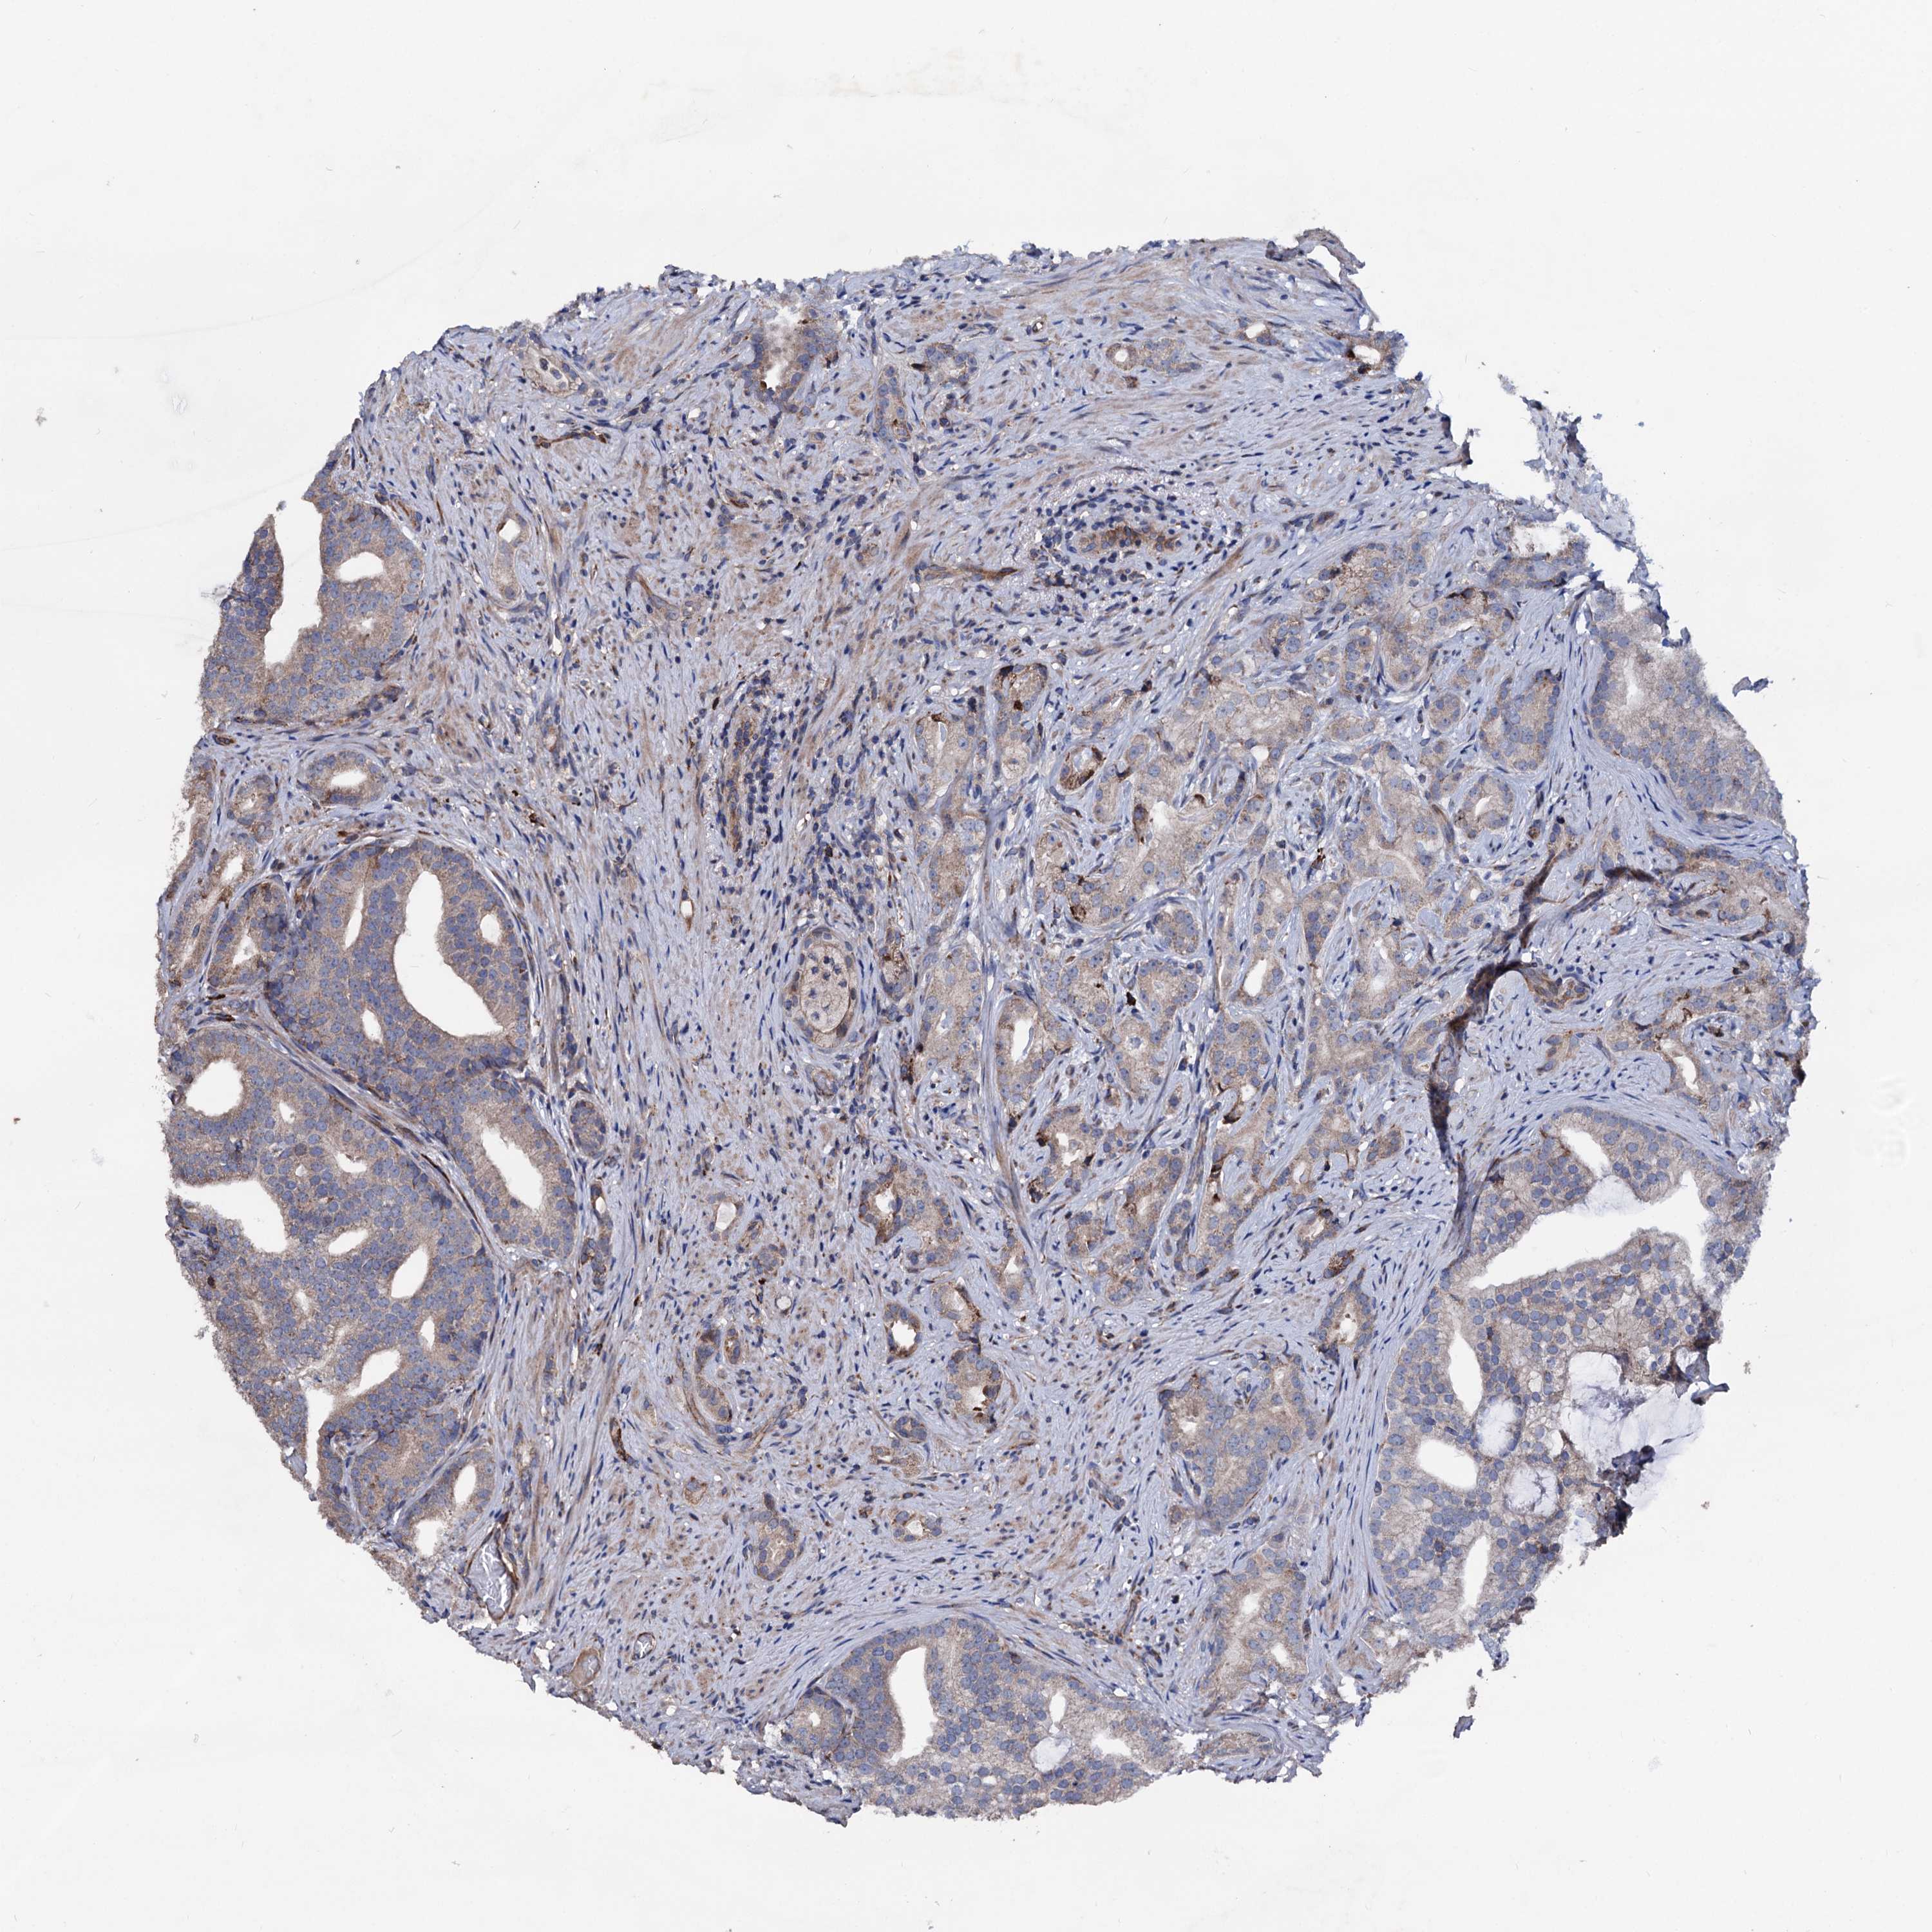

PROSTATE CANCER - Protein expressioni

A mouse-over function shows sample information and annotation data. Click on an image to view it in a full screen mode. Samples can be filtered based on level of antibody staining by selecting one or several of the following categories: high, medium, low and not detected. The assay and annotation is described here.

Antibody stainingi

Antibody staining in the annotated cell types in the current human tissue is reported as not detected, low, medium, or high, based on conventional immunohistochemistry profiling in selected tissues. This score is based on the combination of the staining intensity and fraction of stained cells.

Each image is clickable and will lead to virtual microscopy that enables deeper exploration of all samples and also displays staining intensity scores, fraction scores and subcellular localization as well as patient and tissue information for each sample.

Antibody HPA039089

Staining

High

Medium

Low

Not detected

Intensity

Strong

Moderate

Weak

Negative

Quantity

>75%

75%-25%

<25%

None

Location

Nuclear

Cytoplasmic/membranous

Cytoplasmic/membranous,nuclear

Adenocarcinoma, NOS

Adenocarcinoma, High grade

Adenocarcinoma, Low grade